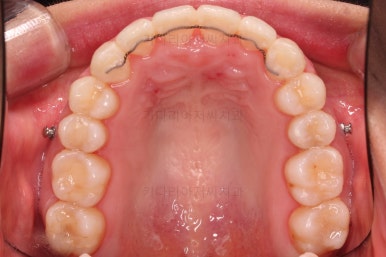

상하좌우 총 4개의 미니스크류를 이용해서 치열을 뒤로 당겨줍니다.

종료 시 사진입니다.

중앙선, 교합, 치아배열 모습 모두 양호해졌습니다.

입매도 본인이 원하는 수준으로 딱 멈춰드렸고, 적절하게 자연스럽게 약간 들어가고 마무리가 되었습니다.

전반적으로 매우 만족하신 치료가 되었습니다.